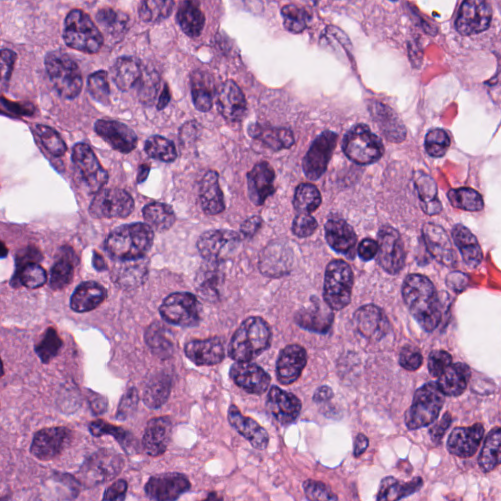

As an essential part of digital pathology, histopathology image analysis is playing increasingly important role in cancer diagnosis, which can provide direct and reliable evidence to diagnose the grade and type of cancer. This paper deals with nuclei segmentation, an important step in histopathological image analysis. The purpose of nuclei semgentation is not only counting the number of nuclei but also obtaining the detailed information of each nucleus. So unlike nuclei detection, here the outputs are the contour of each nucleus instead of only the position of their central points. Hence we can exactly extract each nucleus from the image and make it available for further analysis. For example, the features of the individual nucleus and the distribution of nuclei clusters can be used to grade and classify status of breast cancers [3, 4]. Because of appearance variation such as color, shape, and texture, nuclei segmentation from histopathological images could be very challenging, as illustrated in Fig.1, in which it is very challenging even for human to recognize and segment all nuclei within the images. Fig.1(a) and Fig.1(b) illustrate two histopathological images from different organs. Fig.1(c) and Fig.1(d) are two histopathological images from same organ but have different cancer grade.

H&E stain is the most widely used stain protocol in medical diagnosis. Typically, the nuclei of cells are stained to blue by Haematoxylin while cytoplasm is colored to pink by Eosin. But in practice, the color of H&E stained images could vary a lot due to variation in the H&E reagents, staining process, scanner and the specialist who performs the staining, as shown in Fig.1. A few H&E stain normalization methods[23, 24, 25] have been proposed to eliminate the negative interference caused by color variation. We tried two of them[23, 25] to normalize the raw H&E stained images. For our segmentation algorithm, we did not find any considerable difference between these two normalization methods. Particularly, the result shown in experiment section III is generated based on the images normalized by the method in [23]. Given a target image, this method is able to convert one image’s color into the target image’s color space based on sparse non-negative matrix factorization(NMF). We choose one best stained H&E image as the target and convert other images into its color space. According to the recommendation in [23], the hyper-parameter should be set between 0.01 and 0.1. In our experiment, is set to 0.1.